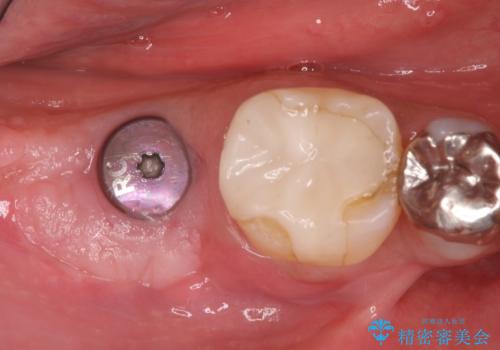

抜歯後十分な骨の回復が認められず、単独の骨増生を行った後にインプラントを埋入しました。

インプラント埋入時に骨が足りない場合にはインプラント埋入前に骨増生を行います。また、インプラント周囲の角化歯肉が不足した場合は角化歯肉の移植も行うことがあります。

どちらの治療もインプラントの長期予後を高めるために必要な治療です。